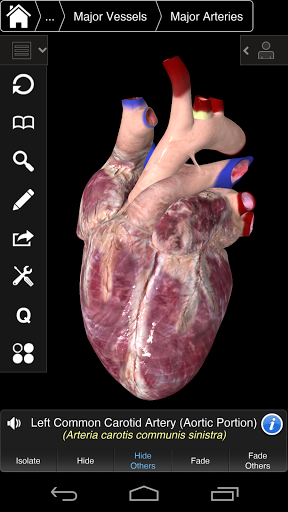

⁃también incluye el cerebro y el corazón

---- Más de 4,000 estructuras anatómicas altamente detalladas

---- Corregir la pronunciación de audio para cada estructura

---- Nomenclatura latina para cada estructura anatómica